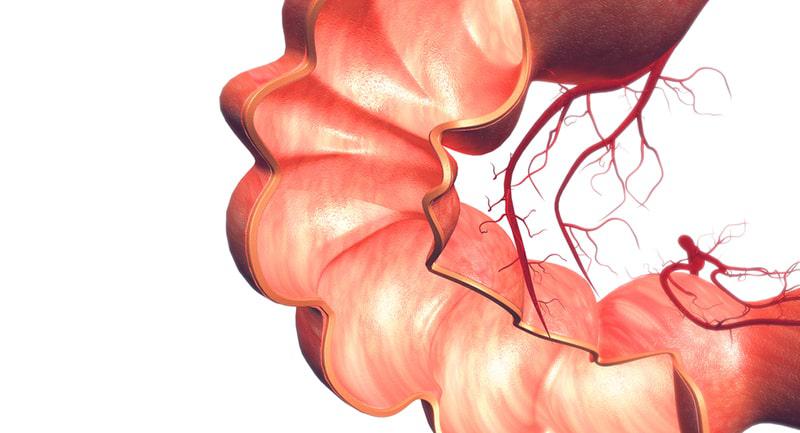

Bağırsak yaraları, sindirim sisteminde oluşan hasarlardır ve çeşitli sağlık sorunlarına yol açabilir. Belirtileri arasında karın ağrısı, ishal ve yorgunluk bulunur. Tedavi yöntemleri, ilaçlardan cerrahi müdahalelere kadar değişir. Erken tanı önemlidir.

Bağırsakta Yara Belirtileri ve Tedavisi Bağırsak yaraları, sindirim sistemi içerisinde meydana gelen hasar veya yaralanmalar olarak tanımlanabilir. Bu durum, çeşitli sağlık sorunlarına yol açabilir ve bireylerin yaşam kalitesini ciddi şekilde etkileyebilir. Bağırsak yaralarının tanınması ve tedavi edilmesi, hastanın genel sağlığı açısından son derece önemlidir. Bu makalede, bağırsakta yara belirtileri, nedenleri ve tedavi yöntemleri ele alınacaktır. Bağırsakta Yara Nedenleri Bağırsak yaraları genellikle çeşitli faktörlerden kaynaklanan iltihaplanma veya enfeksiyon sonucunda ortaya çıkar. Bu faktörler arasında şunlar bulunmaktadır:

Bağırsakta Yara Belirtileri Bağırsak yaralarının belirtileri, yaraların büyüklüğüne, konumuna ve nedenine bağlı olarak değişiklik gösterebilir. Genel olarak, aşağıdaki belirtiler gözlemlenebilir: